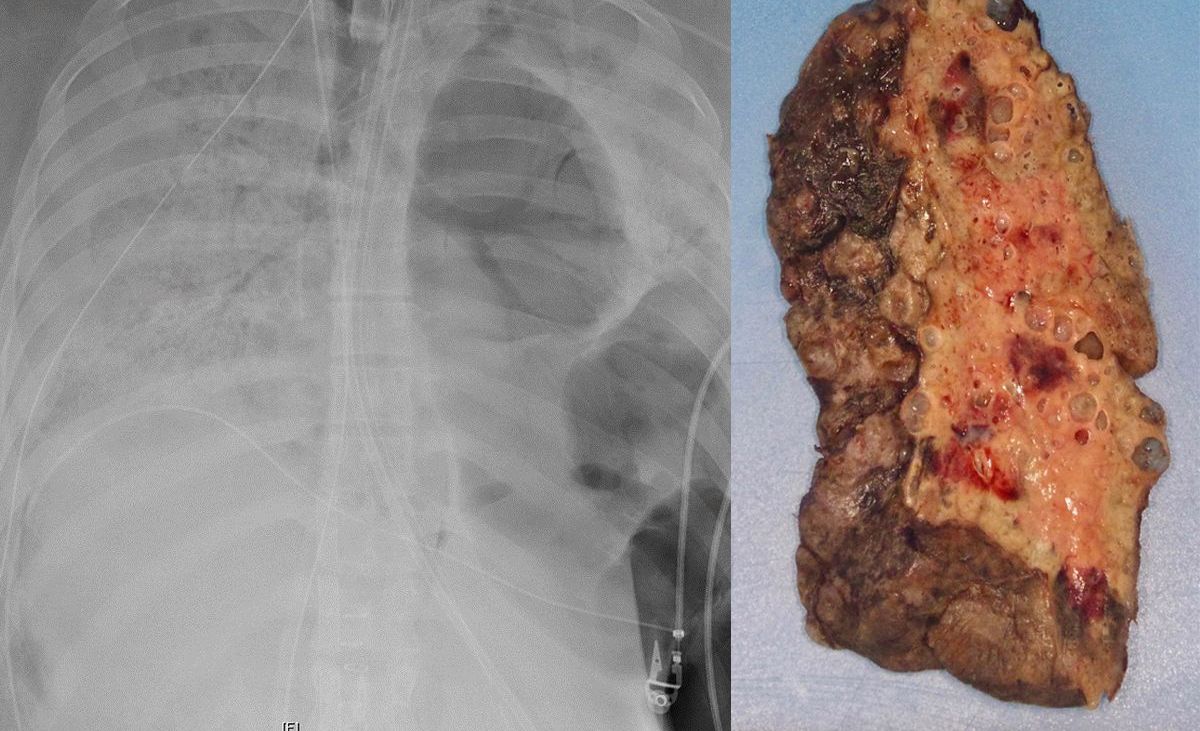

El daño en los pulmones era irreversible. Crédito: Northwestern Medicine | Cortesía

Según la información, la paciente pasó seis semanas en un respirador artificial. Pudo recuperarse del coronavirus, pero el daño en los pulmones era irreversible. La mujer fue puesta en la lista para transplantes, pero la operación solo era autorizada si una nueva prueba de COVID-19 era negativa.